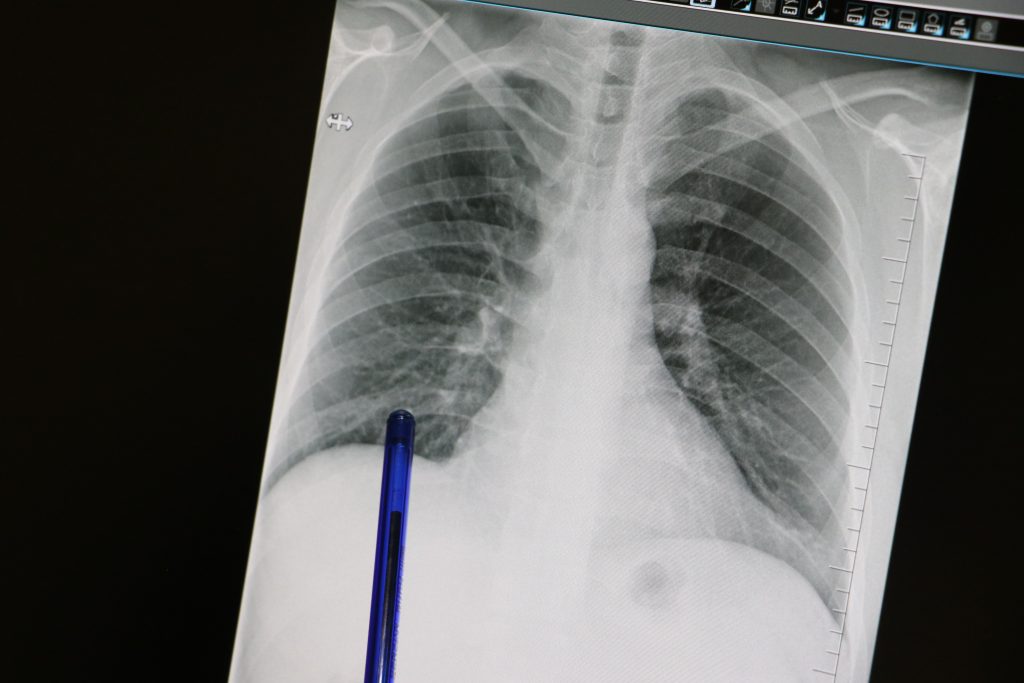

“Her öksürük basit bir soğuk algınlığı değildir. Zatürre, erken tanı konulmadığında ölümcül seyredebilen ciddi bir akciğer enfeksiyonudur. Özellikle çocuklarda, 65 yaş üzeri bireylerde, kronik kalp, böbrek ve akciğer hastalığı bulunanlarda ağır seyredebilir. Bu nedenle belirtiler başladığında vakit kaybetmeden bir uzmana başvurmak gerekir”

“Hastalığın en yaygın belirtileri yüksek ateş, öksürük, balgam, göğüs ağrısı, nefes darlığı ve halsizlik, erken tanı tedavinin başarısını büyük ölçüde arttırıyor. Zatürreye karşı en etkili korunma yönteminin zatürre (pnömokok) ve grip aşısı vurdurmak. Aşı, hastalığın hem görülme sıklığını hem de ölüm oranlarını ciddi ölçüde azaltır. Özellikle risk grubundaki bireylerin her yıl düzenli olarak aşı yaptırması hayati önem taşır. Ayrıca bağışıklık sistemini güçlendirmek için dengeli beslenme, hijyen kurallarına dikkat edilmesi, sigara ve alkol kullanımının bırakılması lazım, Zatürre tedavi edilebilir bir hastalıktır, ancak ihmale gelmez. Unutmayın, her öksürük masum değildir”